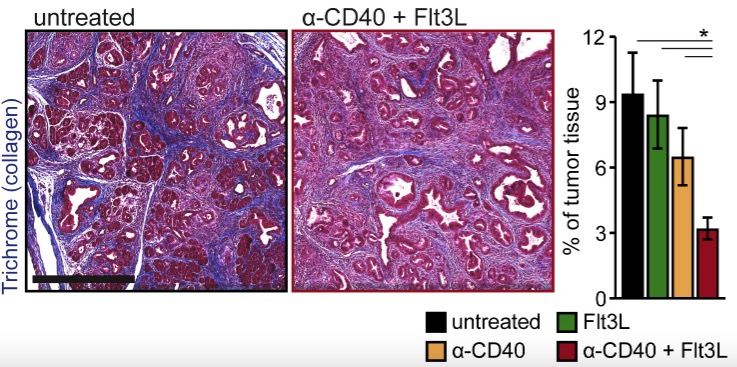

Dendritic Cell Paucity Leads to Dysfunctional Immune Surveillance in Pancreatic Cancer

doi:10.1016/j.ccell.2020.02.008